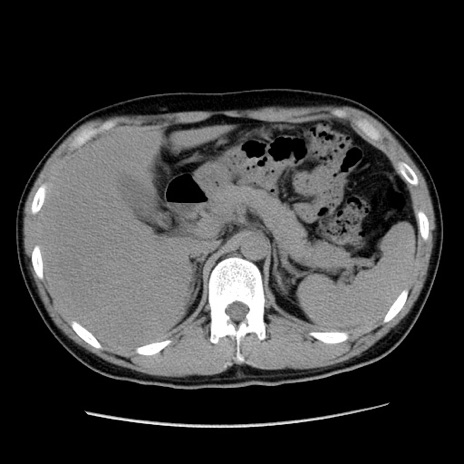

冠状断像

【症例】20歳代 男性

【主訴】心窩部痛

【現病歴】今朝より上腹部痛あり。一旦軽快していたが再度出現したため救急要請。昨日夕に白身の魚を含む刺身を食べた。

【身体所見】BP 136/89mmHg、HR 74/min、BT 37.0℃、腹部:膨満、軟、心窩部に圧痛あり。反跳痛なし、筋性防御なし、腸雑音やや亢進あり。

【データ】WBC 17700、CRP 0.48